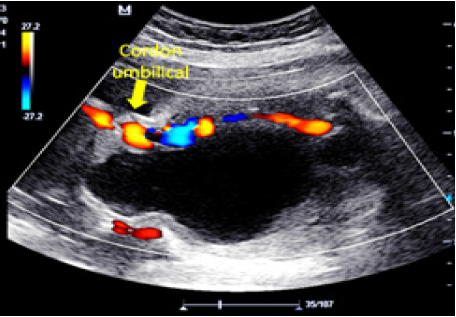

Además, ventriculomegalia, atresia ano rectal, cardiopatía con displasia en ambas válvulas pulmonares, transposición de grandes arterias y miocardiopatía hipertrófica a expensas de ventrículo derecho, que hace sospechar de complejo polimalformativo incompatible con la vida, y se indica interrupción del embarazo. Sin embargo, la paciente decide continuar con la gestación y en nueva apreciación perinatal a las 17 semanas más 6 días de gestación se descarta ventriculomegalia, atresia ano rectal y cardiopatía, no obstante, se aprecia corazón con 2 nódulos ecogénicos en ventrículo izquierdo, riñones con ectasia de 8 mm, megavejiga de drenaje parcial de 90 x 72 x 65 mm con dilatación de uretra proximal (signo de ojo de cerradura) y quiste de cordón umbilical de 29 x 21 mm, realizándose amniocentesis genética que reporta cariotipo 47XY+13 (Figura 2), a la vez se realiza vesicocentesis descompresiva.